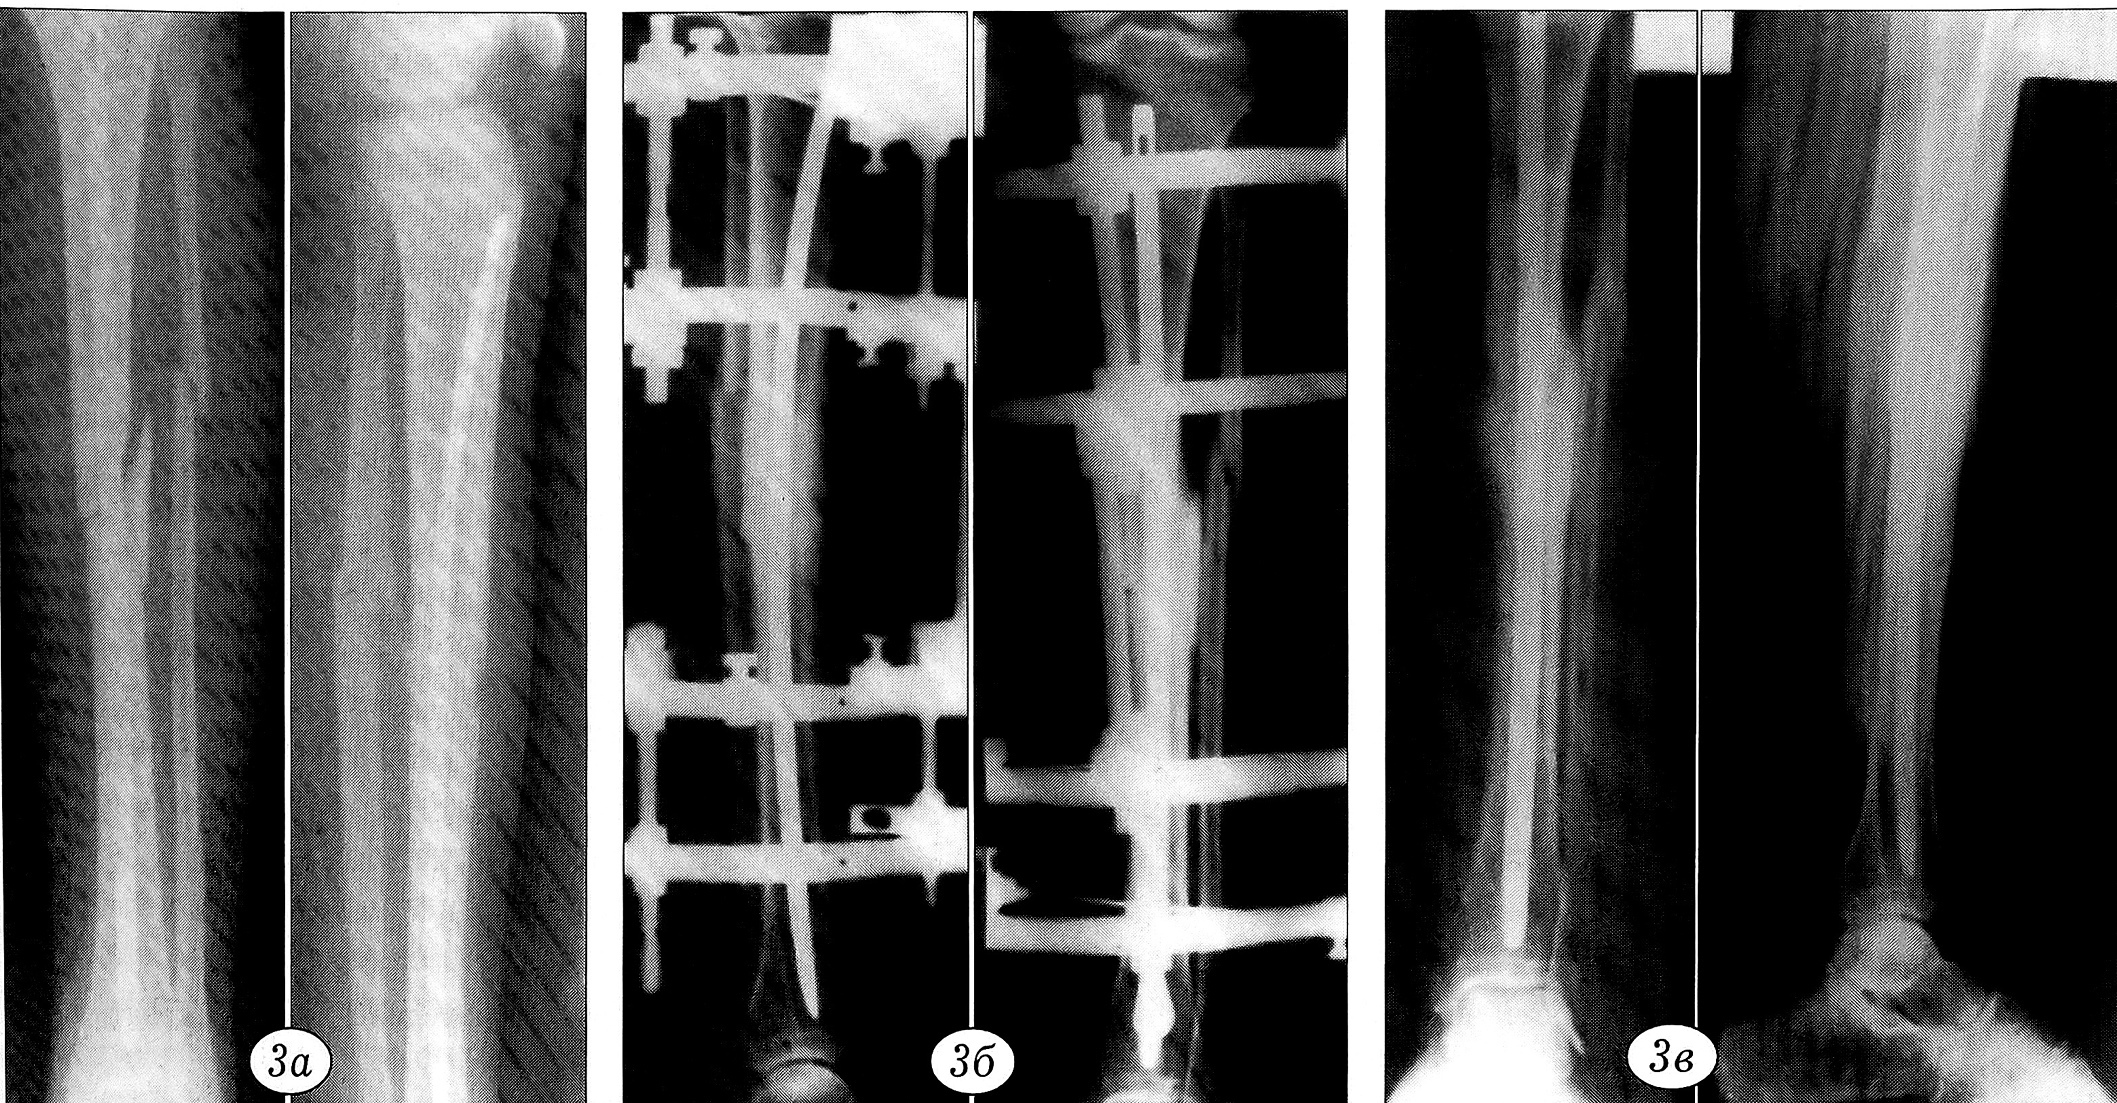

Рис. 3. Пример 3.Рентгенограммы больной В.a — несросшийся перелом большеберцовой кости через 4 мес после интрамедуллярного остеосинтеза металлическим штифтом;б — после наложения аппарата наружной фиксации;в — спустя 4,5 мес: перелом сросся, аппарат удален.

Пример 3. Больная В ., 20 лет, получила закрытый оскольчатый перелом диафиза костей левой голени (сбита автомобилем). В больнице по месту жительства произведен остеосинтез отломков большеберцовой кости стержнем. Перелом не сросся. При поступлении в ЦИТО через 4 мес после травмы клинически и рентгенологически определяется несросшийся перелом большеберцовой кости (рис. 3, а). Без удаления штифта наложен облегченный аппарат наружной чрескостной фиксации, состоящий из 4 скоб со спицами, при помощи которого произведена фиксация костных отломков с их взаимным давлением (рис. 3, б). Через 4,5 мес отмечено сращение перелома, аппарат удален (рис. 3, в).